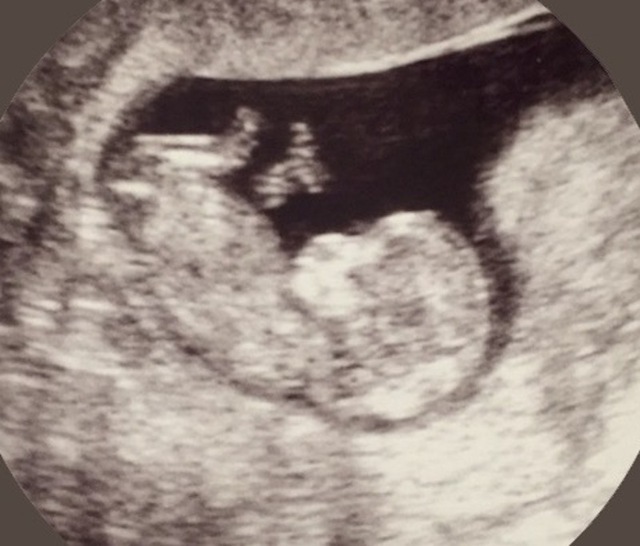

12週0日(12w0d・性別不明)|どどどこ さん(26歳)

エコー写真撮影時のエピソード:

体の上のやつは、赤ちゃんの手です。 手をこっちに向けて振ってくれてるみたいで、とてもお気に入りです!

上の子もこれを見て、手を振り返していました! とても微笑ましい姿で 産まれてくるのが楽しみです!